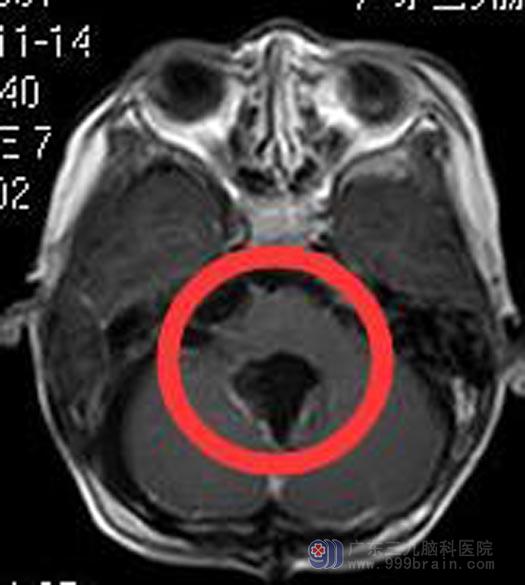

完善检查后,综合神经外科鲁明主任主刀,在全麻下行后正中入路小脑蚓部肿瘤切除术,显微镜下见灰白色肿瘤组织,位于四脑室,与小脑蚓部关系密切,血供一般,从肿瘤下缘逐步分块切除,手术过程中延髓及小脑半球保护良好,术后欣欣未再出现头晕呕吐症状,病理结果提示:间变性室管膜瘤WHO III级。

▲手术后